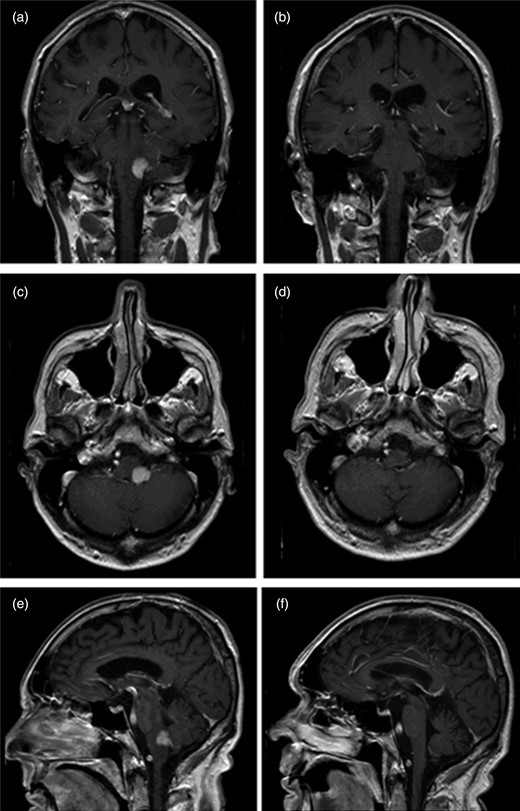

Gadolinium-enhanced magnetic resonance imaging (MRI) of the brain revealed a homogenously enhancing, sharply demarcated 13 mm diameter lesion in the left posterior and lateral midbrain extending into the inferior cerebellar peduncle, with some adjacent oedema, suggestive of primary lymphoma (see Fig. 1). Stereotactic brain biopsy confirmed diffuse large B-cell lymphoma (DLBCL) and subsequent bone marrow biopsy and computer tomography (CT) imaging showed no evidence of lymphoma at any additional anatomical site.

Gadolinium-enhanced T1-weighted MRI images (panes lettered with coronal (a), axial (b) and sagittal (c) sections) showing a homogenous enhancement of a clearly demarcated lesion in the left posterior and lateral midbrain with extension into the inferior cerebellar peduncle.